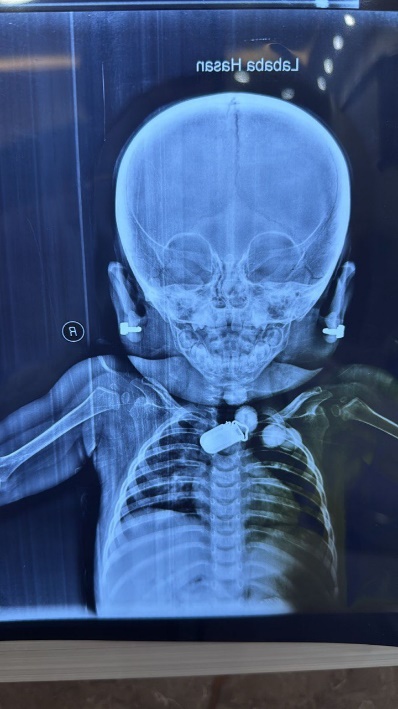

Craniofacial: Broad forehead, thick eyebrows, long eyelashes, flat nasal bridge.

Skeletal: Short broad hands/feet, clenched fists, bilateral clubfoot.

Figure 10: Facial features of the patient with HPMRS (Mabry syndrome) Frontal photograph showing coarse facial appearance with a broad forehead, thick eyebrows, long eyelashes, full cheeks, and a flat nasal bridge, typical of PIGV-related HPMRS.

Clinical Correlation

Our patient’s manifestations—severe hypotonia, seizures, craniofacial dysmorphism, cortical blindness, and skeletal deformities—are consistent with previously reported PIGV-related cases [4,6,10]. Congenital heart disease (ASD) has occasionally been described in this subtype [7,11].